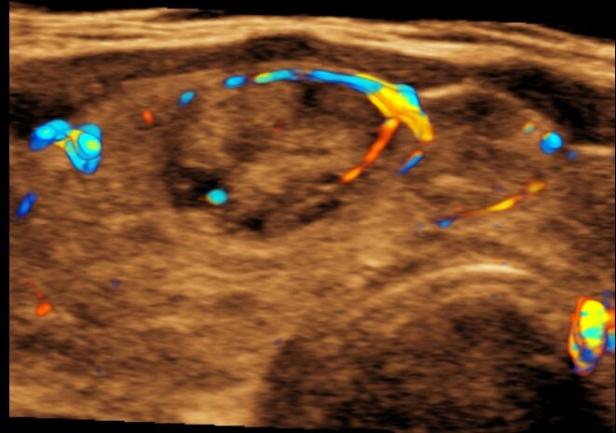

B超是甲状腺疾病检查最常规的检查项目,它没有辐射、无创,并可根据图像观察结节大小、位置、形态、边界、内部回声均匀与不均匀以及囊性、实性及混合性。当发现自己甲状腺长了“结节或瘤子”了,不必惊慌,首先,根据B超检查,初步明确它的性质,也就是说是“良性”还是“恶性”,其中大部分可以可通过B超做出明确性质的诊断。

但是,由于B超的分辨率及病灶与组织密度基本一致情况下就不能做出明确诊断。因此,需要更加进一步检查。大家知道,病理学诊断是医学的最后诊断,也是医学诊断的“金标准”,那么怎样才能获得病变的组织或细胞呢?就是在B超实时引导和监视下通过一根很细针插入病灶内,获取病灶内的组织或细胞,进行病理检查,明确性质。